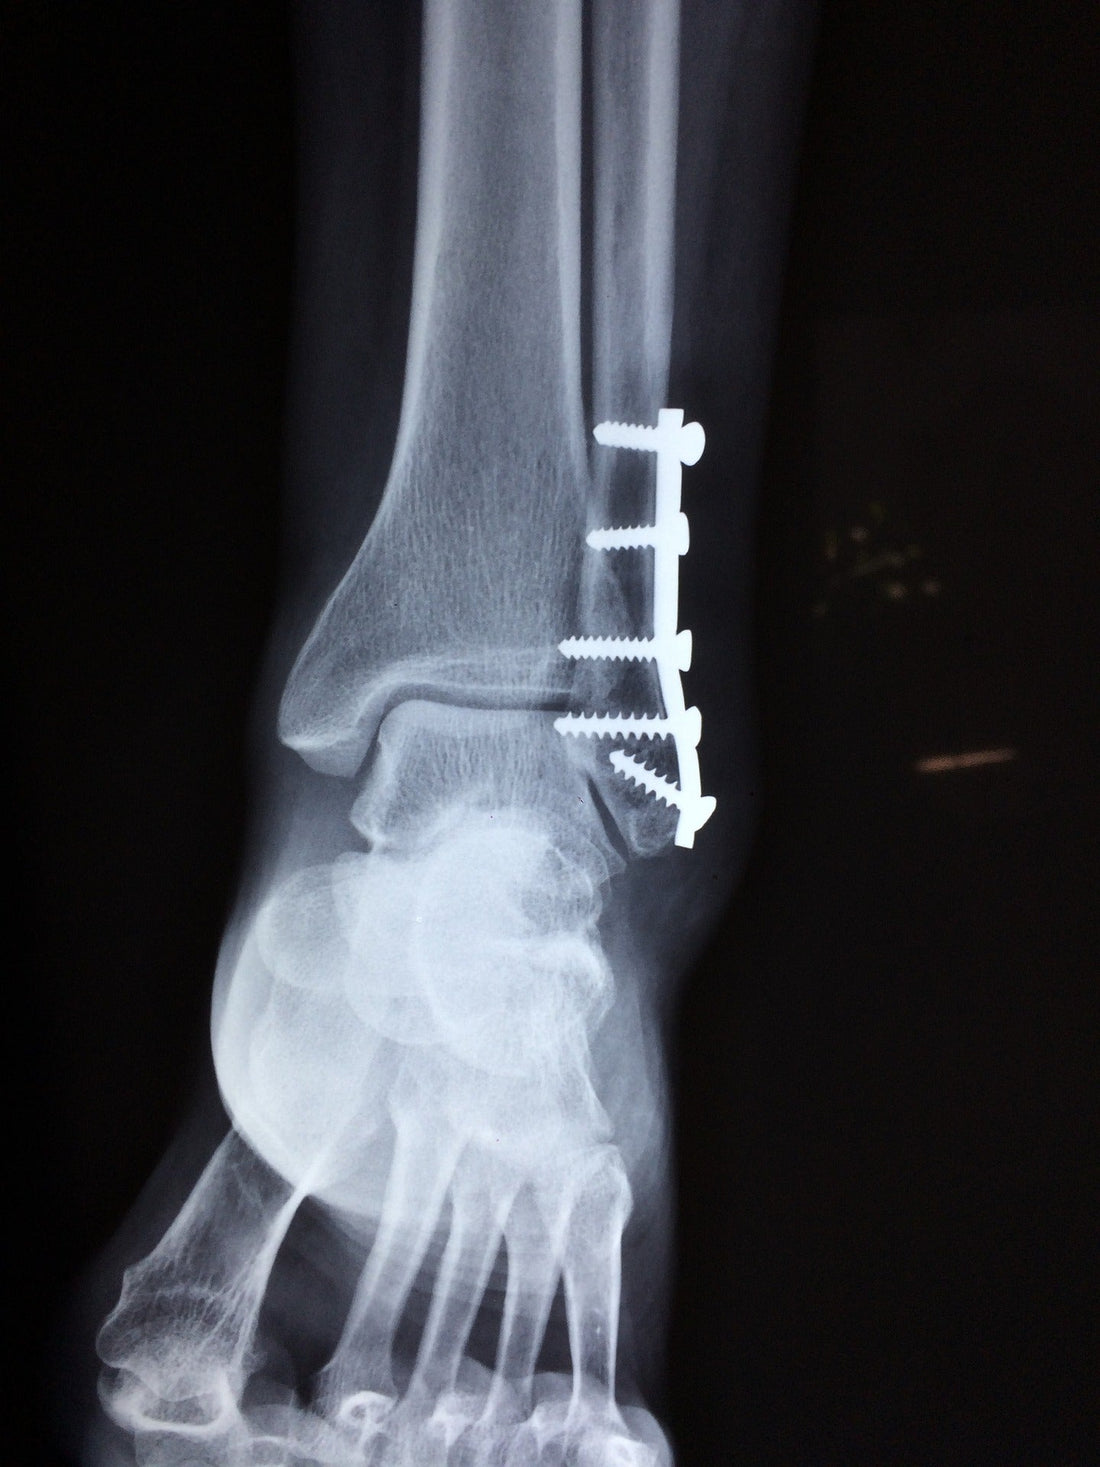

- Ankle fracture surgery - The broken bone fragments are moved back to the correct position inside the ankle and stabilizing items, such as screws and metal plates, are inserted to support correct healing.

- Ankle fusion/arthrodesis - Damaged tissue or cartilage is removed from the surface of the ankle and then the ankle is surgically fused back together using metal plates and screws.

- Ankle replacement - Damaged parts of the ankle (or the whole ankle joint) are removed and replaced with the prosthetic equivalent(s) - usually plastic or metal. Screws and surgical glue can be used to help secure everything together.